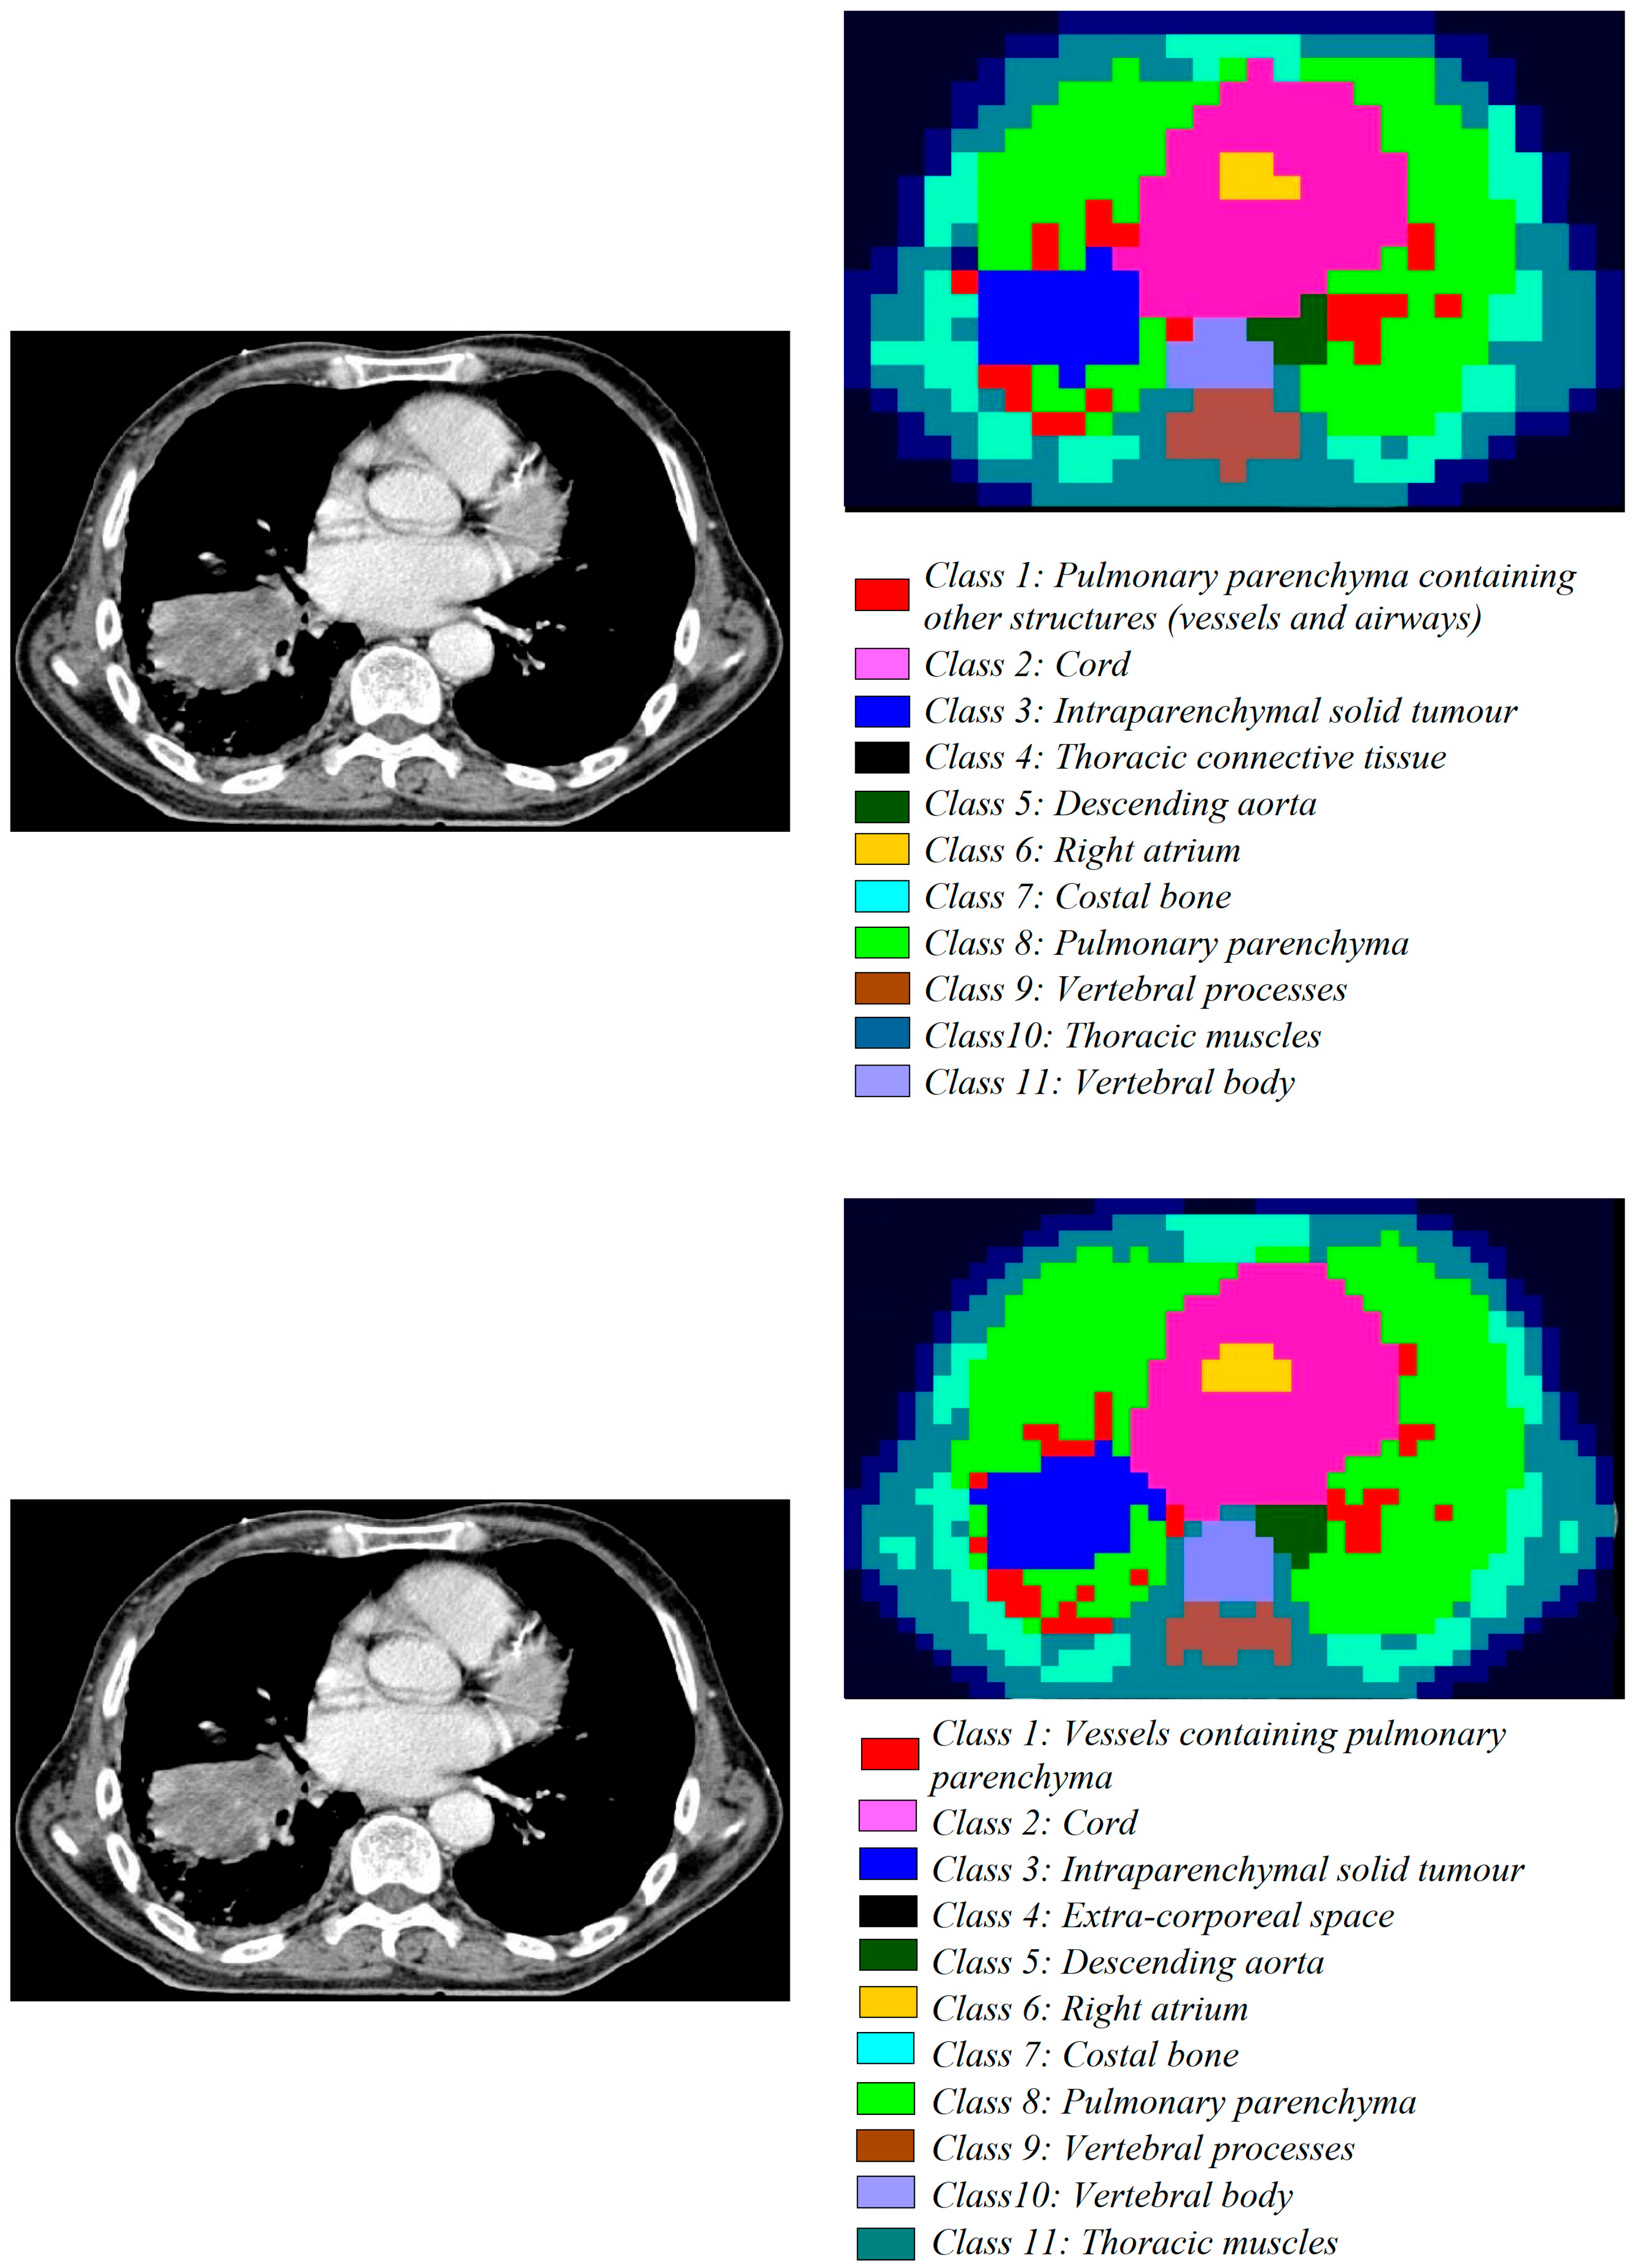

- The second dataset of images is from the patients with lung tumours; there are 11,210 CT images and 25 pathology slices collected from 6 patients. From these, we selected 10 images from 2 patients with lung adenocarcinoma. Usually, lung adenocarcinomas show an admixture of many architectural patterns such as acinar, papillary, micropapillary, lepidic, and solid growth patterns [32,33].

- The third dataset of images is extracted from a collection of 52,072 images from 422 patients with non-small cell lung cancer (NSCLC) [34]. For these patients, pre-treatment CT scans lung tumours; manual delineation by a radiation oncologist of the 3D volume of the gross tumour volume and clinical outcome data are available in [31] for the Lung1 dataset. Typically, lung cancer pathology can identify two groups of cancer cells: small cell lung cancer (SCLC) and non-small cell lung cancer (NSCLC). Then, the last ones, the NSCLC, are divided again into squamous cell cancer (SCC), large cell cancer, and lung adenocarcinoma. Finally, in situ (ISA) and invasive are the two types of lung adenocarcinoma.

3.1.2. Medical Images

| Non-small cell lung cancer | Computer tomography (CT) scan | 1/1 | avg. 1802 × 884 | 1372 × 672 | 4 × 4 | 57,624 |